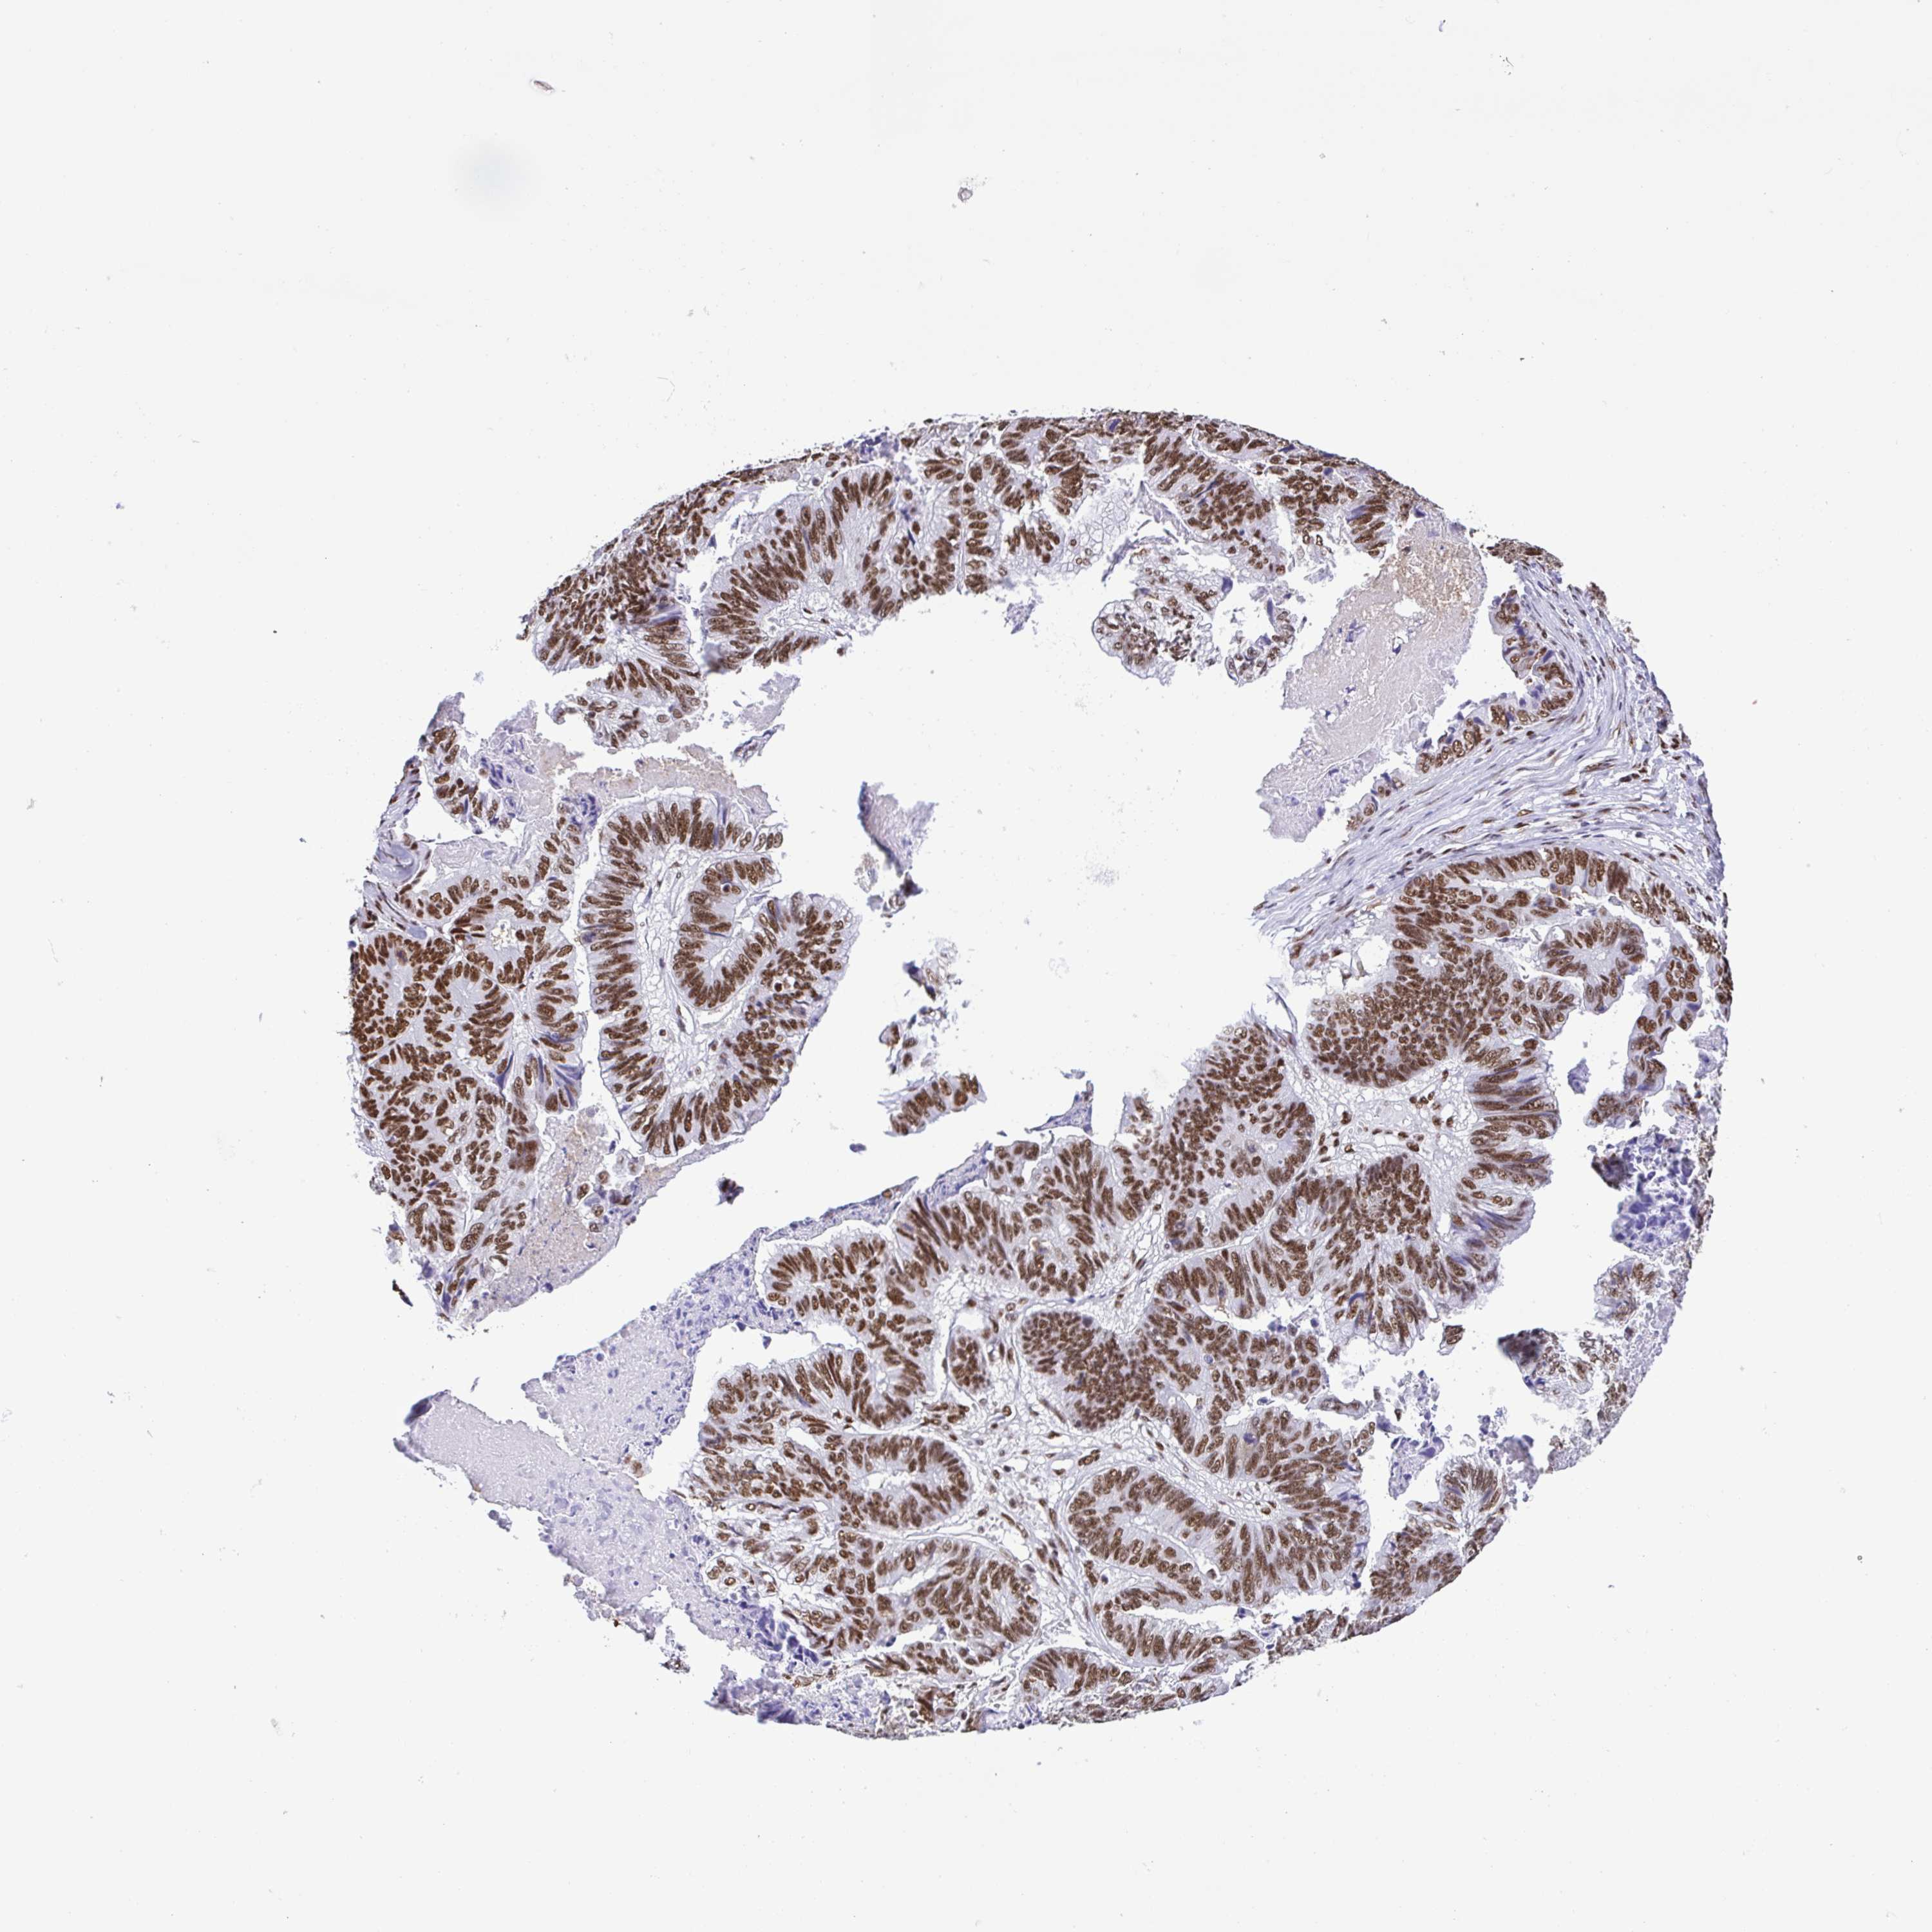

STOMACH CANCER - Protein expressioni

A mouse-over function shows sample information and annotation data. Click on an image to view it in a full screen mode. Samples can be filtered based on level of antibody staining by selecting one or several of the following categories: high, medium, low and not detected. The assay and annotation is described here.

Note that samples used for immunohistochemistry by the Human Protein Atlas do not correspond to samples in the TCGA dataset.

Antibody stainingi

Antibody staining in the annotated cell types in the current human tissue is reported as not detected, low, medium, or high, based on conventional immunohistochemistry profiling in selected tissues. This score is based on the combination of the staining intensity and fraction of stained cells.

Each image is clickable and will lead to virtual microscopy that enables deeper exploration of all samples and also displays staining intensity scores, fraction scores and subcellular localization as well as patient and tissue information for each sample.

Antibody HPA064033

Antibody CAB010066

Staining

High

Medium

Low

Not detected

Intensity

Strong

Moderate

Weak

Negative

Quantity

>75%

75%-25%

<25%

None

Location

Nuclear

Cytoplasmic/membranous

Cytoplasmic/membranous,nuclear

Adenocarcinoma, NOS

Adenocarcinoma, High grade